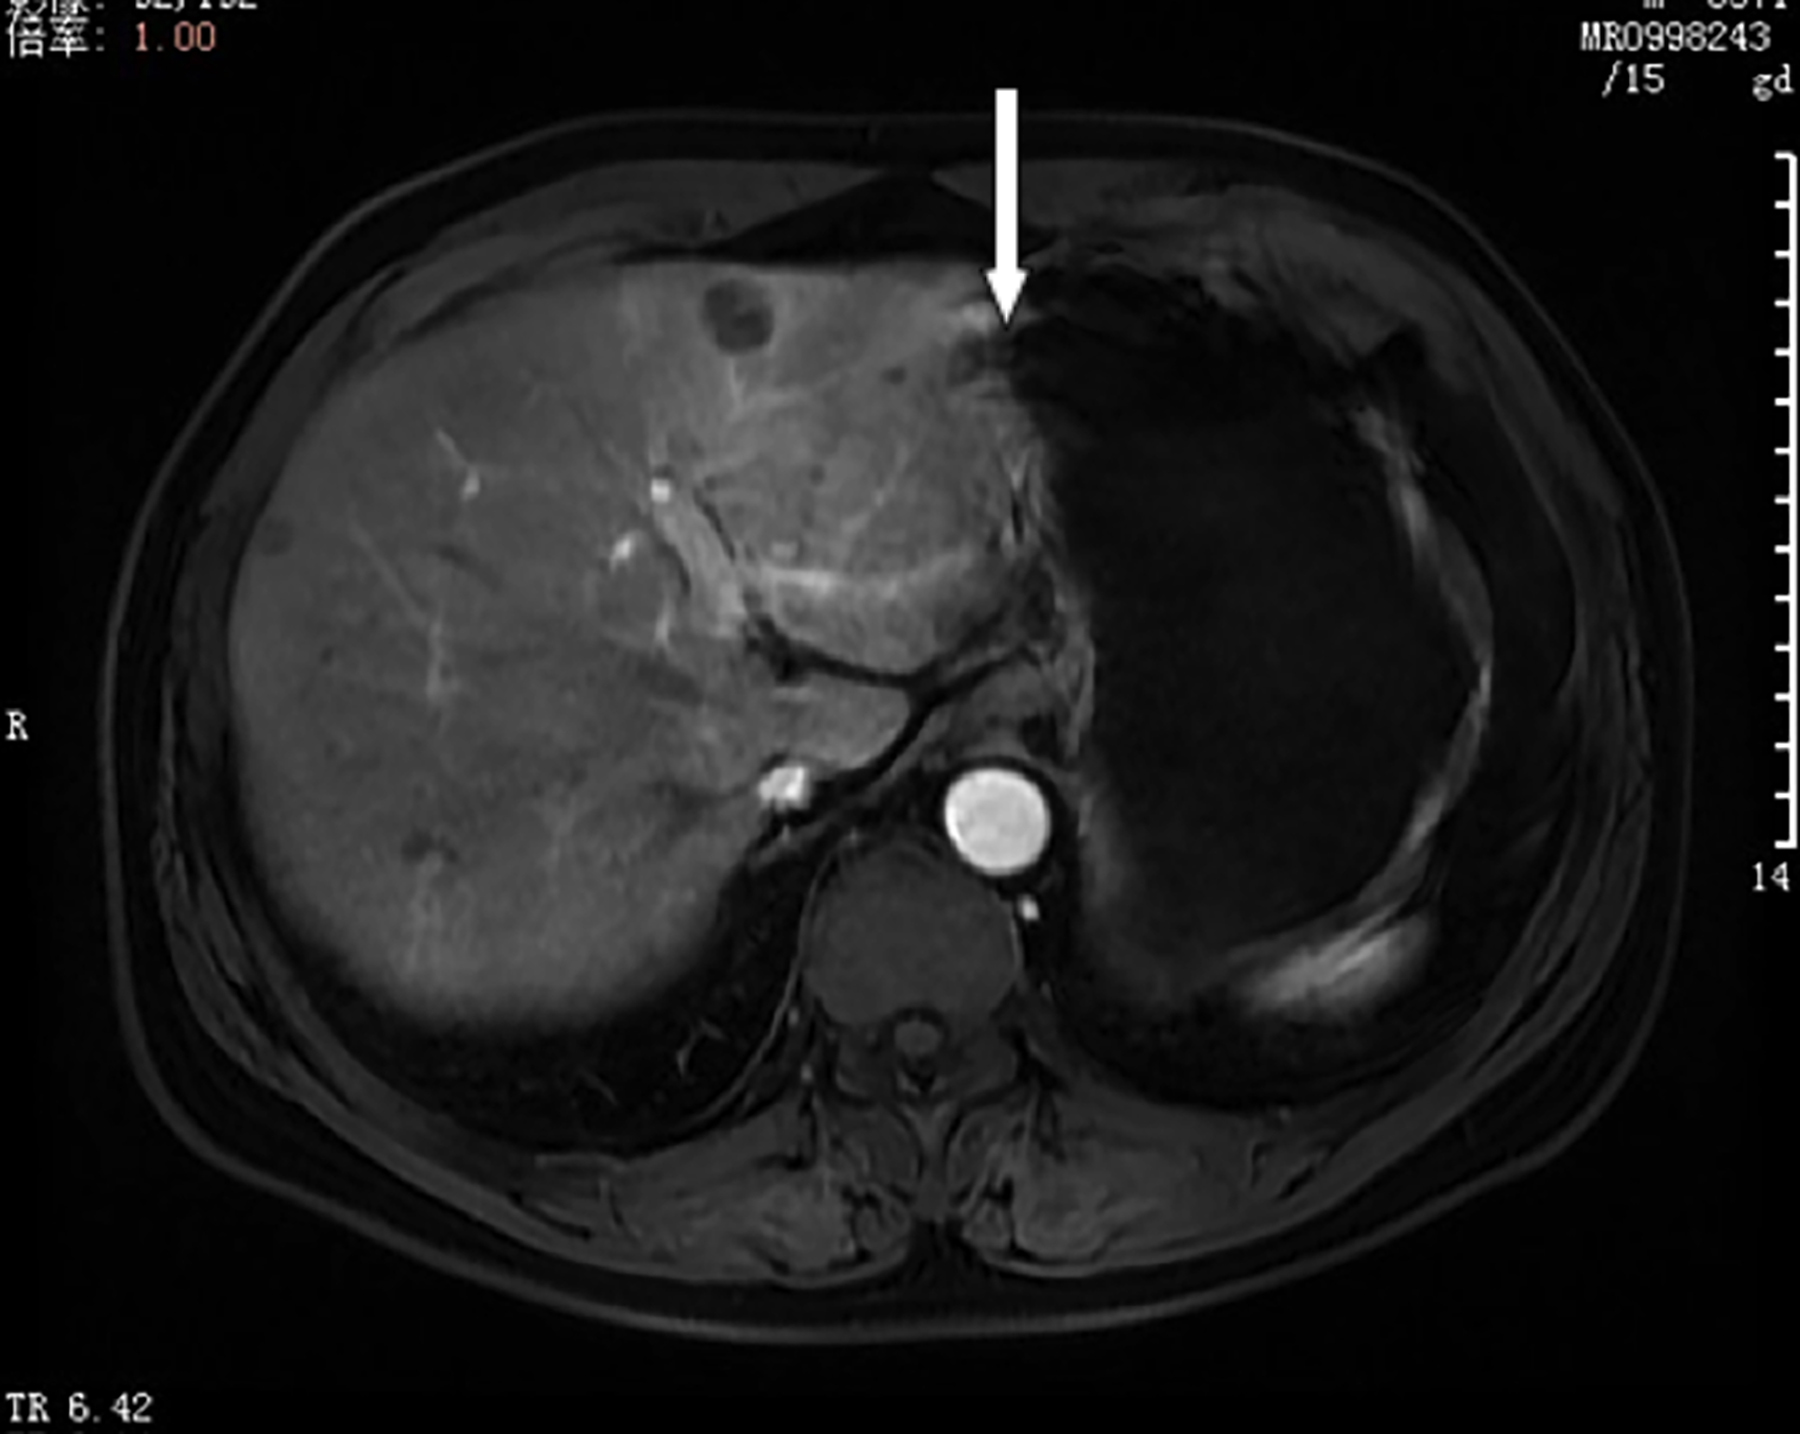

Figure 1: Computed tomography of the tumour.

A 57-year man was admitted in 2019 because of regurgitation and belching for more than 2 years. He denied nausea, vomiting, hematemesis, melena, or weight loss. The patient had been previously healthy. He had a history of smoking for more than 30 years. His father had been diagnosed with hypertension and diabetes mellitus. His mother and two younger sisters were healthy. Physical examination on admission was unremarkable. The laboratory examinations were almost normal, including complete blood count, hepatorenal functions, and tumour markers (alpha-fetoprotein, carcinoembryonic antigen and carbohydrate antigen 19-9). Computed tomography (CT) of the whole body ruled out bony metastases. Both contrast-enhanced CT and MRI revealed thickening of the wall of the gastric angle with enlarged surrounding lymph nodes.